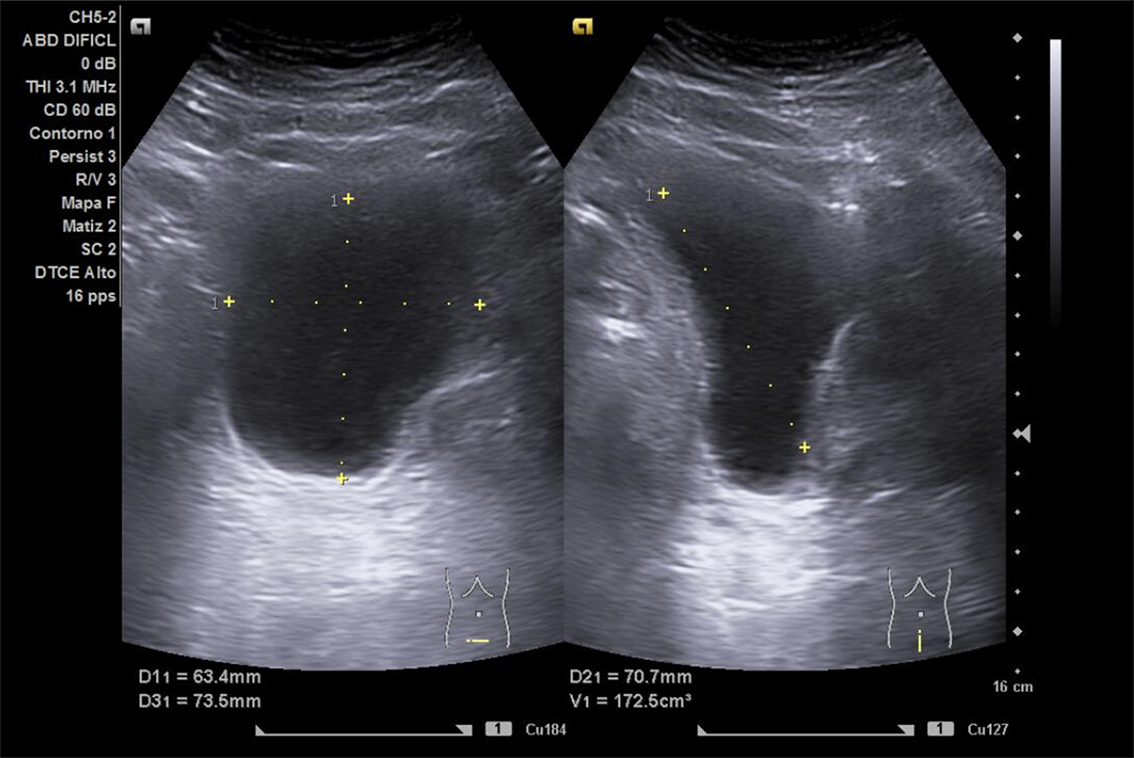

Se realiza ECO POCUS en la que se aprecia riñón derecho de morfología y tamaño normal. Riñón izquierdo con hidronefrosis grado III. A nivel de vejiga, bien replecionada se aprecia masa a nivel de pared izquierda adyacente a unión ureterovesical de 1.8 x 2,7 cm Ausencia de jet izquierdo.